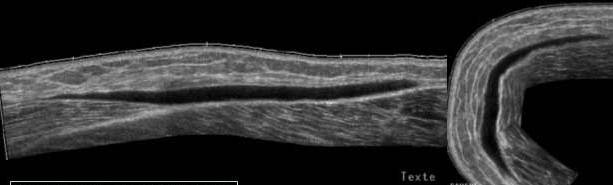

Cicatrice fibroasa a dreptului femural

Traumatism prin soc direct in urma cu 3 sapt.

Imagini calcare in muschi, superficial, departe de diafiza

femurala.

Persistenta unei mici componente lichidiene in contact cu

calcificarile

Masa hiperecogena, difuz delimitata,

Compresibila, in adductor, avand o

structura tubulara

Corespondenta IRM